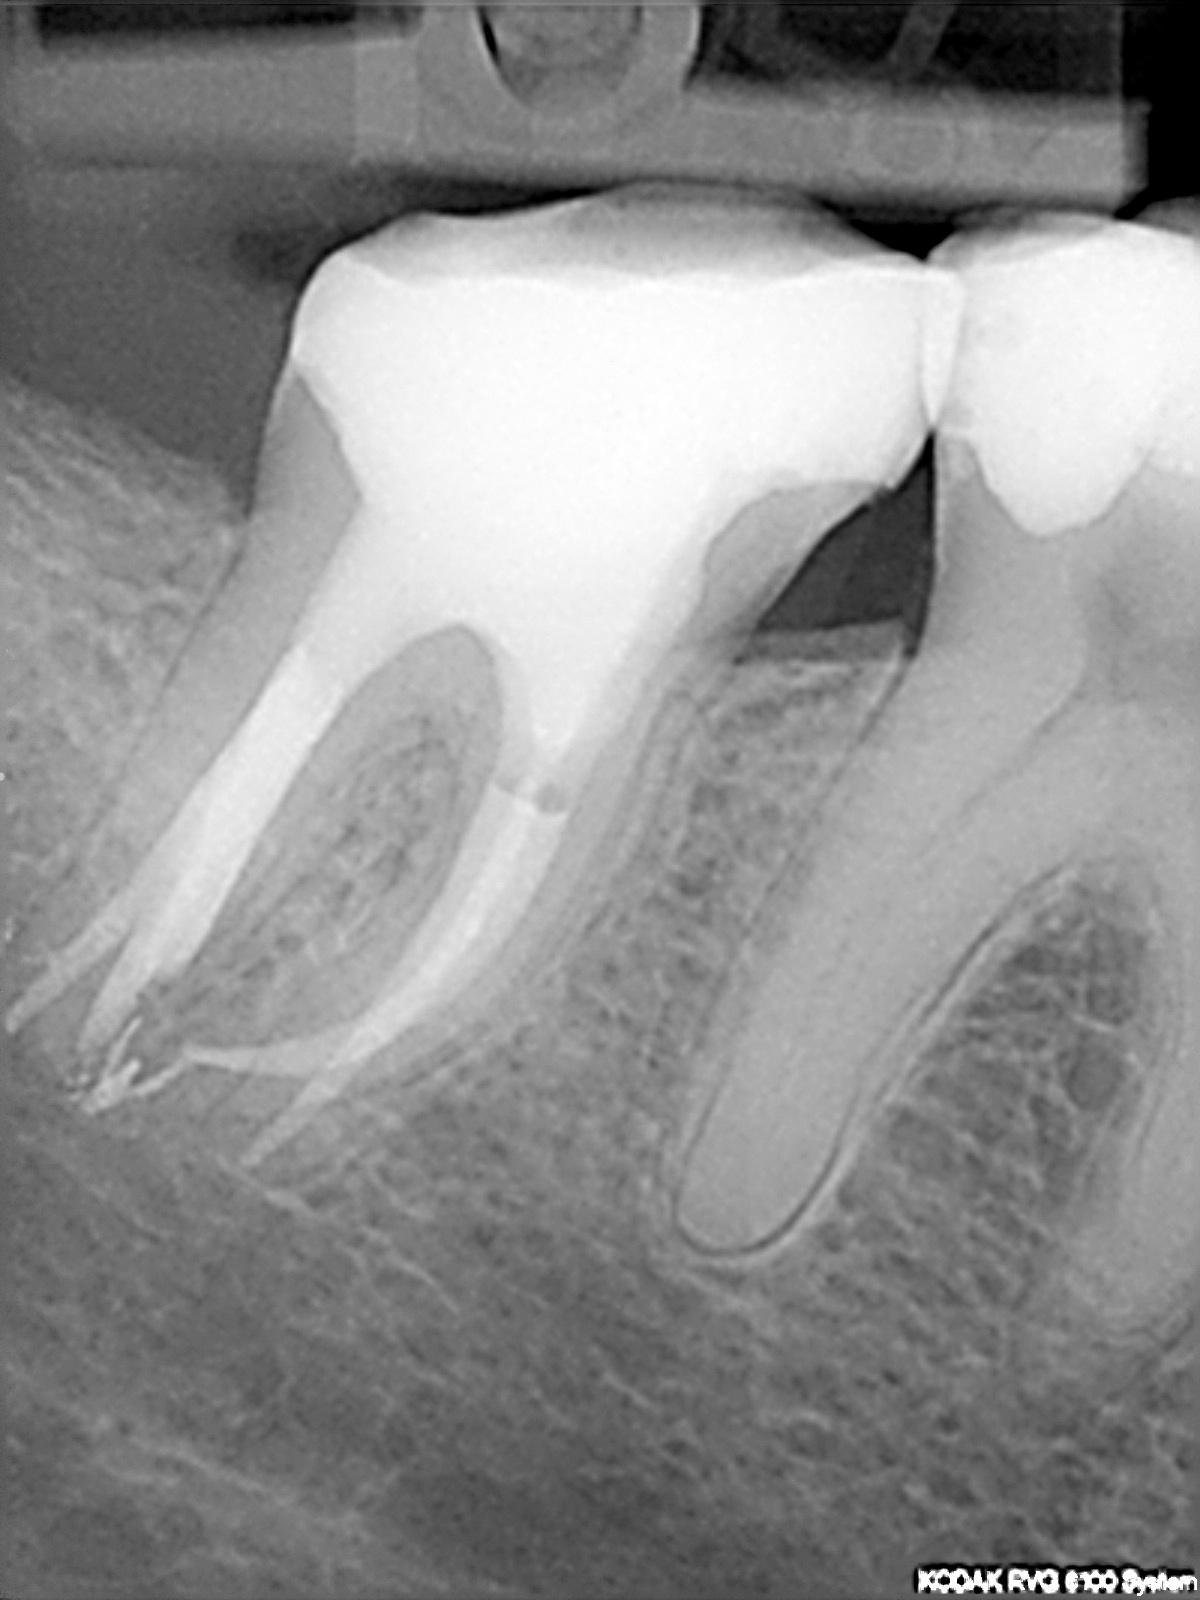

SDR14

1200 × 1600

SDR® und X-tra base

SDR®